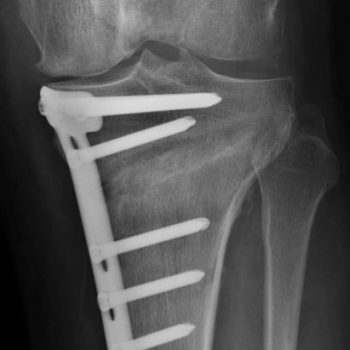

Essa cirurgia designada por Osteotomia, é uma cirurgia desafiante na qual é realizado um corte preciso no osso e se corrige o desvio do membro levando a uma melhoria dos sintomas e possibilidade de retomar as atividades recreativas e laborais, com elevado grau de satisfação.